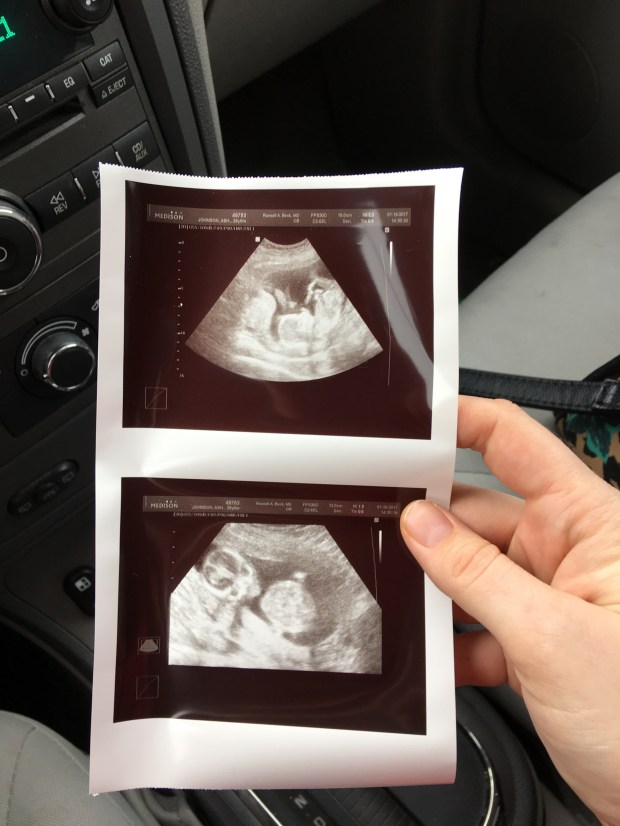

I was telling my Doctor Beck how we believed I was 12 weeks and I lay down on the table he felt my stomach, “yep, there is a baby in there. But I don’t think you are 12 weeks”. He then busted out the ultrasound and BAM! There was my baby. Beautiful, healthy, only one, and moving. After some quick measurements, Dr. Beck informed us I am actually SIXTEEN weeks along. I jumped ahead a whole month! We are 2 weeks from being half way there. Oh my goodness! I’m still taking that one in.

Top: cute side shot with baby’s feet in the air. Bottom: scary alien shot with baby looking right at you.